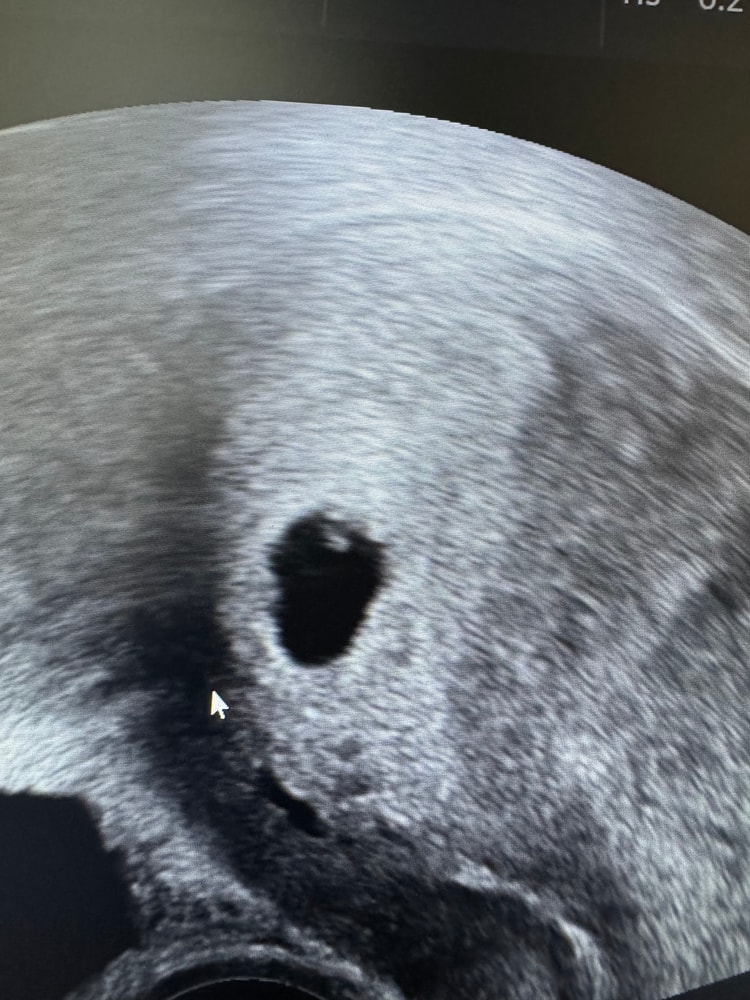

Узи на 5 неделе 3 дня. (4-5недель) эмбриональный

Здравствуйте всем, я была на своем первом узи недавно, врач определил плодное яйцо в полости матки, через 2 недели сказал приходить слушать сердечко. Я спросила, что это за точка в плодном яйце? Он сказал, что это уже будущий она или он… а я смотрю.. и почему то сомневаюсь, не рано? Точно ли это эмбрион уже виден?

А я вижу и эмбрион, и ЖМ, но могу ошибаться. У подруги в 5,3 тоже так же было. Сверху эмбрион, ниже ЖМ

Это не эмбрион, а желточный мешочек. Но то, что он появился, - хороший знак. Значит, скоро появится эмбрион.

У меня в 5,3 недели тоже видно ПЯ и ЖМ